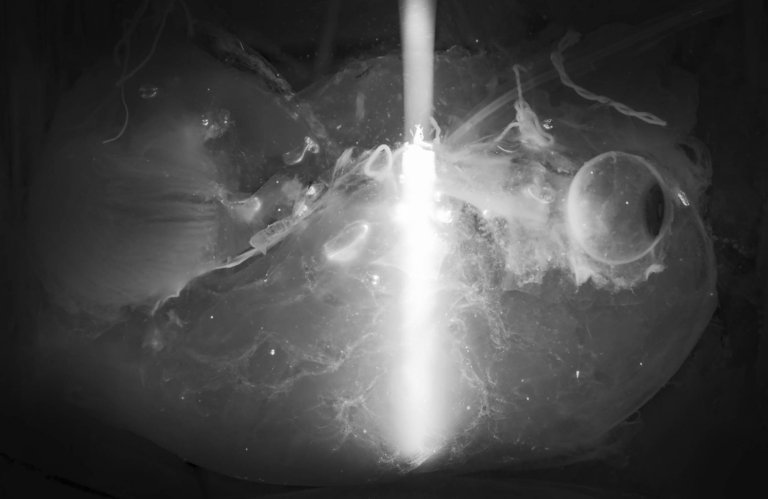

Pela primeira vez, pesquisadores conseguiram tornar transparentes órgãos humanos intactos.

Olhando esses órgãos transparentes ao microscópio, torna-se possível visualizar e mapear estruturas complexas no interior dos órgãos com resolução celular, algo que não é possível com os órgãos em seu estado natural opaco.

Desenvolvimentos recentes no clareamento de tecidos biológicos permitiram aos pesquisadores obter as primeiras visualizações celulares de órgãos biológicos transparentes e intactos em 3D, usando cobaias.

Após testes exaustivos, a equipe descobriu que um detergente chamado CHAPS ([Colamidopropil]dimetilamônio-propanossulfonato), usado nos laboratórios para solubilizar proteínas, consegue fazer pequenos buracos em todos os rígidos órgãos humanos. Isso permite que soluções adicionais viajem profundamente no interior dos órgãos, atingindo centímetros de espessura, e os convertam em uma estrutura transparente.